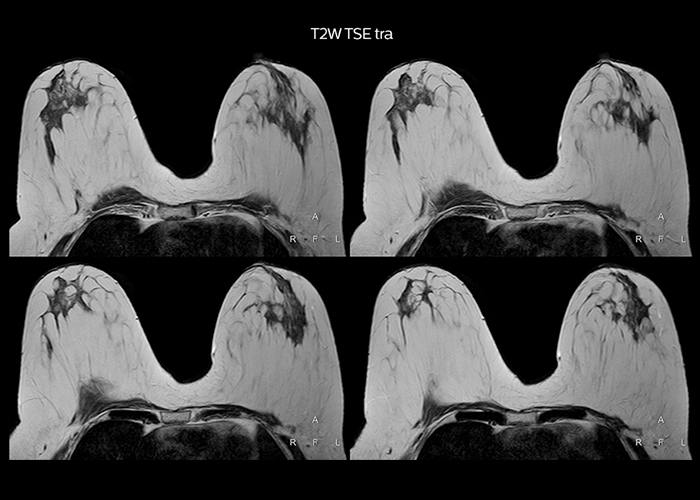

“On average, we scan about 80 patients per day, but on some days we scan well over 100 patients. The scanner is in use 7 days per week, operated 20 hours per day on week days and 8 hours per day in the weekend,” Mr. Tuna says. “To avoid coil changes we plan examinations of similar anatomies back to back, such as head and spine. Multiva helps us here a lot because coils don’t need to be changed frequently. Moreover, thanks to parallel imaging technology and 16-channel HeadSpineTorso and 8-channel MSK coils we are able to achieve excellent image quality. In this way Multiva helped us to increase both image quality and productivity.” “Neurological cases, such as brain and spine imaging, represent the largest share in our MR scanning, followed by musculoskeletal cases. In general, we use simple and basic imaging protocols. But occasionally, we use advanced techniques for problematic cases if necessary.